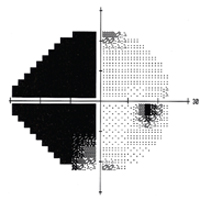

Specialty glaucoma clinics are held throughout the week so that complex glaucoma patients can be seen with fellowship trained glaucoma specialists. Additionally, glaucoma patients are seen in the general clinic with general ophthalmology attendings throughout the week. One resident reads

automated visual field tests one day per week in a one-on-one session. An excellent experience in surgical glaucoma therapy is provided; approximately four glaucoma surgical procedures are done each week, with residents as the primary surgeon in Eye Center cases. Surgical experience is gathered in standard trabeculectomy, MIGS procedures, antimetabolite assisted procedures, peripheral iridectomies, goniotomy, and placement of seton tubes and valves. Residents are expected to become proficient in all procedures as primary surgeon. In addition, experience is gained in cyclodestruction procedures with either cryotherapy, contact YAG or contact diode laser, selective laser trabeculoplasty, thermal laser trabeculoplasties and laser peripheral iridotomies. Emphasis is placed on modern nerve fiber analysis with the OCT. By the end of the training, residents are able to examine and treat all aspects of glaucoma medically and surgically. The Glaucoma Section faculty who participate in the resident continuity clinic include Section Director Michael L. Savitt, MD, MD, Madhu S.R. Gorla, MD, Nina A Goyal, MD, Anjali S. Hawkins, MD, PhD, Brian Herst, MD, Brian J. Jacobs, MD, Hreem Patel, MD, and Rebecca Sarran, MD. -